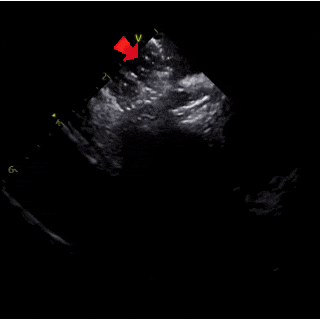

ICE下清楚显示右盘已展开呈球状,钢缆轻轻前推使其贴靠房间隔

ICE下牵拉试验可见封堵器整体移动

ICE下可见封堵器成型良好,左右盘面牢牢夹持房间隔,且无残余分流,封堵手术成功